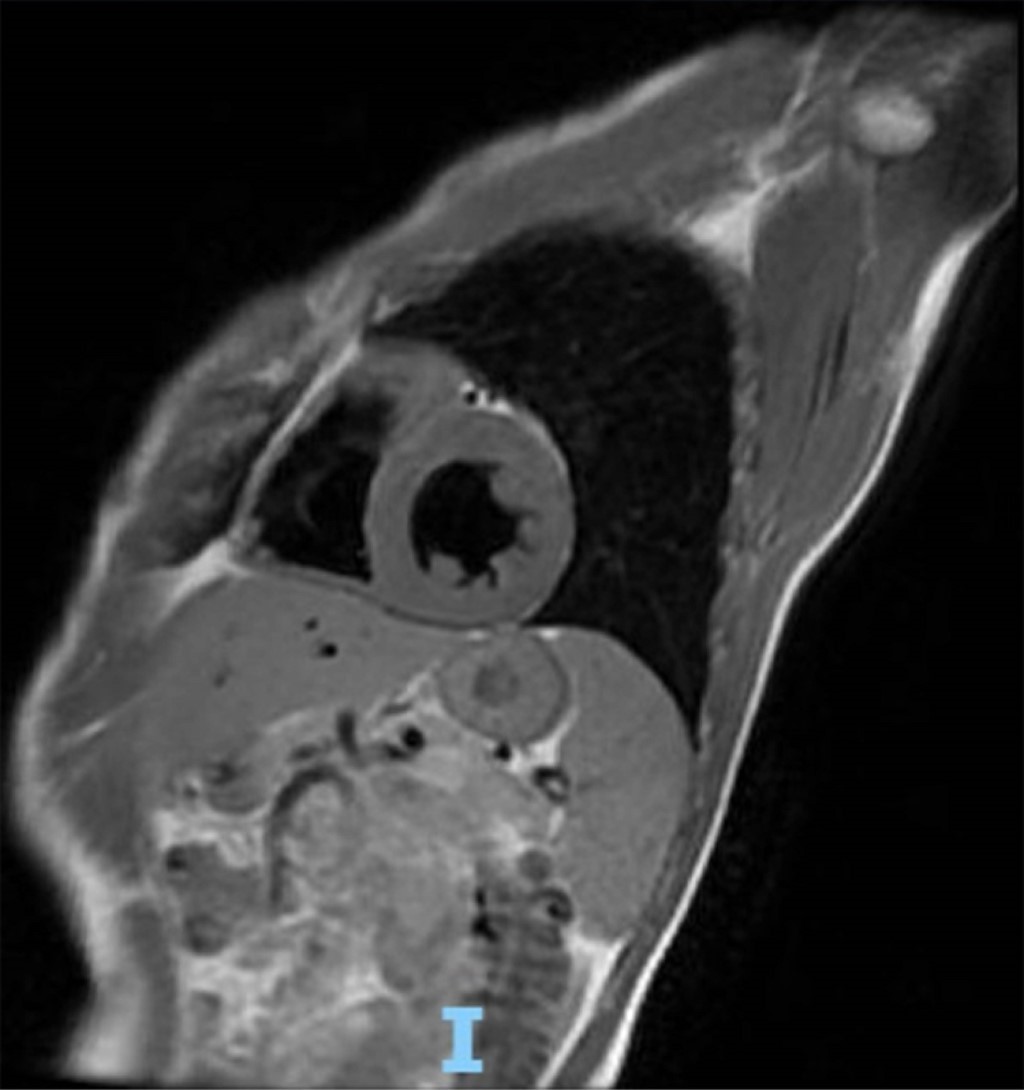

Caso clínico 1: mujer de 41 años, originaria de la Ciudad de México. Sin antecedentes hereditarios de relevancia. Historia de hipertensión arterial sistémica de 12 años de diagnóstico en tratamiento con bisoprolol 5 mg cada 12 horas. Fue sometida a procedimiento quirúrgico por el antecedente de fistula de líquido cefalorraquídeo recidivante. En el seguimiento clínico por cardiología, se realiza resonancia magnética cardiovascular con los siguientes hallazgos en el ventrículo izquierdo: hipertrofia septal asimétrica con grosor máximo de 24.7 mm, a nivel medio 23 mm, pared posterior del ventrículo izquierdo 8 mm, Diámetro diastólico del ventrículo izquierdo de 46 mm, diámetro sistólico del ventrículo izquierdo de 24 mm, con índice de volumen telediastólico de 85.4 mL/m2, e índice de volumen telesistólico de 19.3 mL/m2, la masa miocárdica de es de 212 g, con fracción de acortamiento de 48% y fracción de eyección de 77%. Ventrículo derecho, aurículas y válvulas sin alteraciones morfológicas o funcionales, con diagnóstico de cardiopatía hipertrófica septal asimétrica obstructiva (Figura 1).

Figura 1